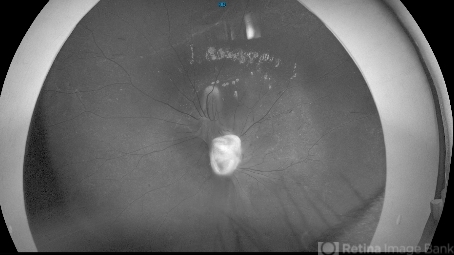

- toxocara granuloma

- 10 year old girl referred for starbismus and red free image showed well demarcted inactive lesion.